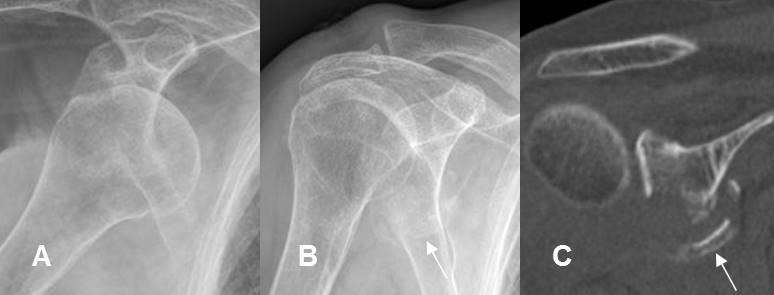

Fig 160. Subluxación anterior.

A: Rx AP de hombro y B: TAC axial. Desalineación anterior de la articulación glenohumeral, con pérdida parcial de la relación articular.